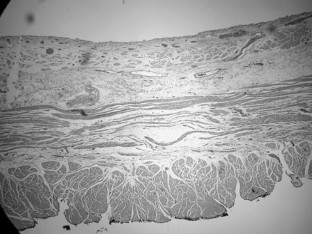

Fig. 2